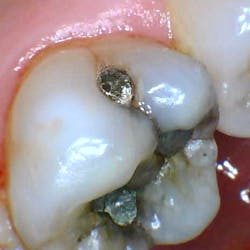

- 62-year-old female, new-patient exam/full assessment

- Asymptomatic tooth no. 14

- Arguably conservative lingual/mesial/distal pit occlusal amalgams with a small fracture on the mesial restoration

- Noted fracture lines across the transverse and mesial marginal ridges as well as lingual and buccal grooves

- Amalgam salt leakage/staining of the tooth with likely caries that’s not clinically or radiographically evident, especially where the amalgam is cracked